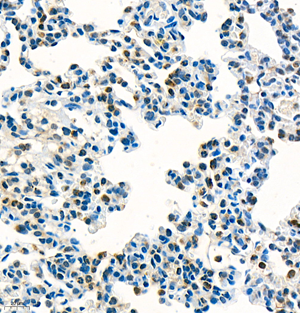

| IHC analysis of mpo (GB11224). Sample: Rat lung+lps (Paraffin), 4% PFA (G1101) 12-24h. Antigen retrieval: Citrate buffer (pH 6.0) (G1201),98°C,20 min. Blocking buffer: 3% BSA in PBS (GC305010), RT, 30min. Primary antibody: 1: 1800, 4°C overnight. Secondary antibody: HRP Goat Anti-Rabbit lgG (GB23303), 1: 200 RT 1h. |